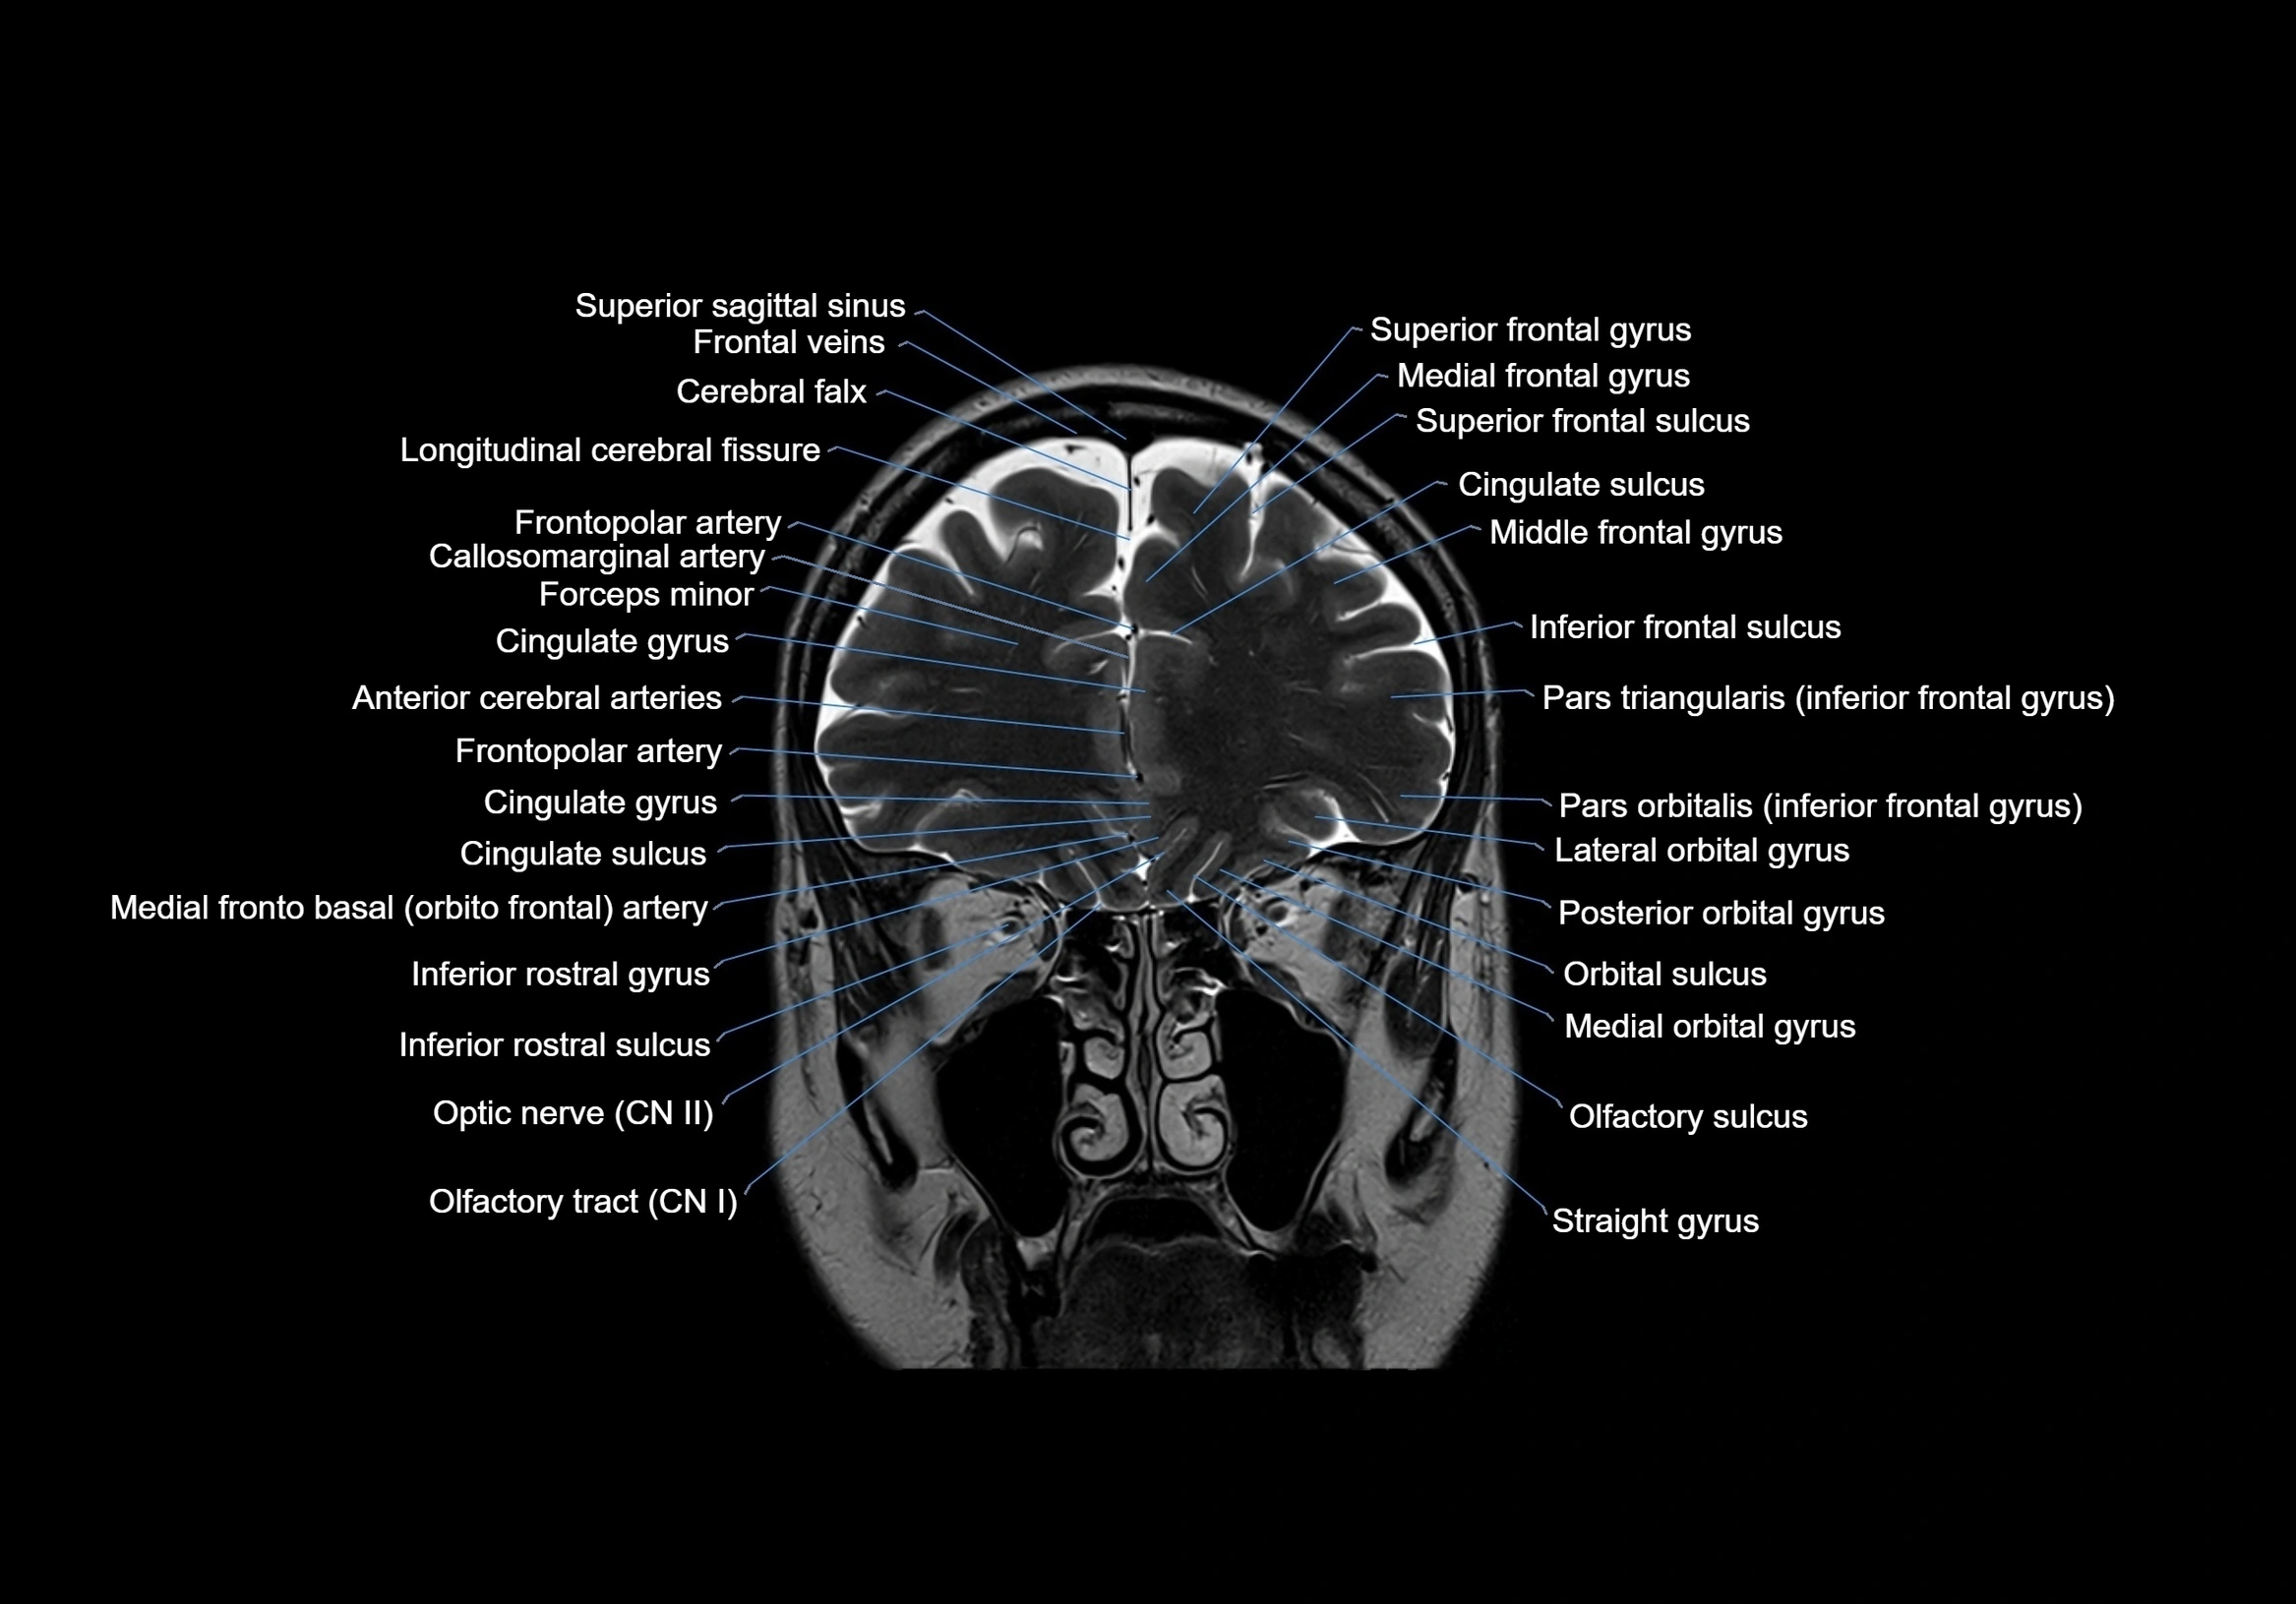

MRI images